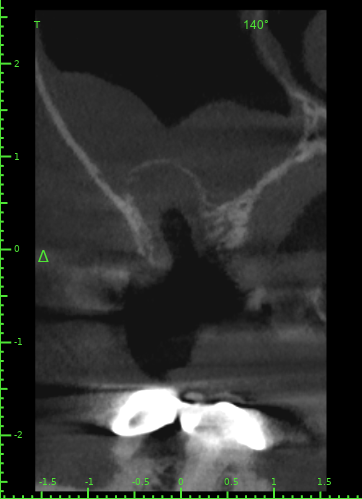

Atcotr Опубликовано 18 июля, 2024 Автор Поделиться Опубликовано 18 июля, 2024 @Женька @red_butler КТ сделано на 17-й день после удаления зуба. Не могли бы вы его посмотреть? Есть ли по вашему мнению свищ или признаки его формирования? Есть ли угроза для 27го импланта? Слизистая в гайморовой пазухе была опухшая задолго до удаления, это не новый процесс. КТ находится по ссылке: https://1drv.ms/f/s!AptB3I-32KWekuk4OkRq7Q6cdU7XcA?e=v69OYx Беспокоит чувство заложенности носа и уха слева после приёма любых жидкостей. Лечащий врач сказал, что небольшие перфорации в 95% случаев зарастают самостоятельно, назначил антибиотик и псевдоэфедрин и следующий приём через месяц. Спасибо за помощь. Ссылка на комментарий

Женька Опубликовано 19 июля, 2024 Поделиться Опубликовано 19 июля, 2024 Материала я, конечно, тут не особо вижу. Возможно он был, но весь вымылся. Перфорация действительно есть. Я бы ждал сейчас заживления и после оценивал формирование сообщения с пазухой. Снимок всю пазуху не вмещает, что там выше возле соустья неизвестно. Ухо, от ситуации на снимке, болеть вряд ли может на мой взгляд. Ссылка на комментарий